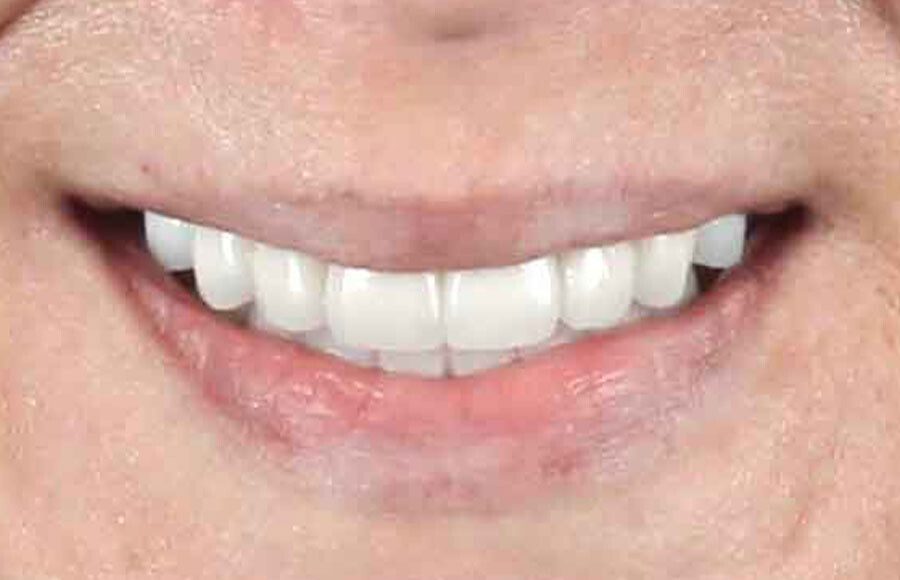

The prototypes are tested in the mouth to ensure we all love the size, shape, and position of the teeth.